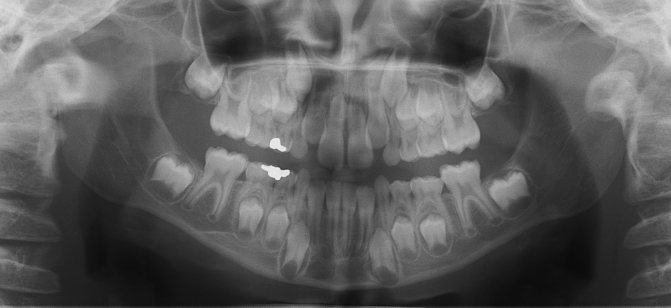

Обычно на 5-7 годах жизни у детей начинается смена молочного комплекта зубов на постоянные. Корни единиц имеют свойство рассасываться. Это приводит к утрате устойчивости, зуб постепенно расшатывается. В этом случае он выпадает сам без помощи стоматолога. Но так происходит не всегда. Можно ли рвать молочные зубы? Врачи отвечают на этот вопрос утвердительно. Однако процедуру удаления проводят по показаниям. Рассмотрим их.

- Задержку рассасывания корня при уже начавшемся росте постоянного зуба.

- Наличие рассосавшегося корня (видимого на снимке) и шатающегося зуба, который уже давно по своим срокам должен был выпасть.

Удалением молочных зубов не зря занимаются именно детские врачи. Все дело в том, что удаление детских зубов требует особенных навыков. Молочные зубки обладают довольно тонкими альвеолярными стенками и имеют более тонкие (и длинные), в сравнении с коренными зубами, корни.

Также имеют значение зачатки постоянных зубов, особенности строения челюсти растущего малыша и смешанный прикус. Одно неосторожное движение – и зачатки постоянных зубов могут быть повреждены.